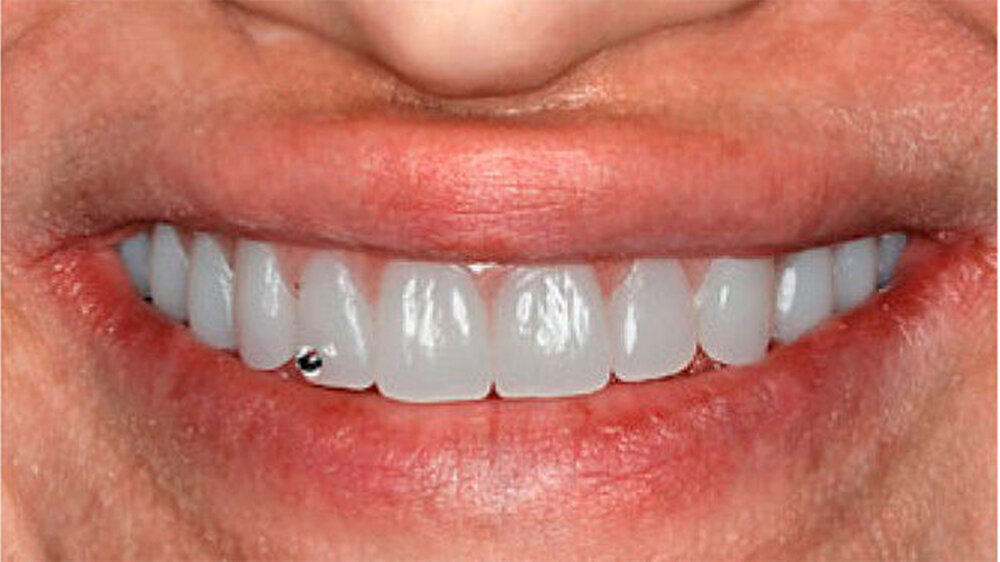

Aufgrund des anatomisch sehr ungünstigen Prothesenlagers war der Erhalt der Restbezahnung im Oberkiefer anzustreben. Nach Kariesexkavation und Wurzelkanalbehandlung konnten beide Zähne mit einer Wurzelstiftkappe versorgt und die alten Prothesen entsprechend umgebaut werden. Im Anschluss an die Meisterabformungen und an die Ausrichtung der Wachswälle wurden die Modelle schädelbezogen einartikuliert, und die Prothesenzähne nach ästhetischen und funktionellen Richtlinien aufgestellt. Eine bilateral balancierte Okklusionsbeziehung konnte umgesetzt werden. Im Oberkiefer wurde eine gerüstverstärkte Totalprothese hergestellt, die auf den beiden Wurzelstiftkappen 16 und 26 verankert war. Im Unterkiefer konnte die Patientin mit einer Totalprothese versorgt werden (Abb. 21 bis 23).

Verbunden mit dem Umstand, dass die Patientin eine ausgeprägte Oligosialie aufweist, ist das Kariesrisiko und hiermit verbunden, auch das Pfeilerzahnrisiko deutlich erhöht. Regelmäßige Kontrolluntersuchungen sind zwingend. Da das Kieferwachstum noch nicht abgeschlossen ist, werden weitere zahnärztliche Behandlungen unumgänglich sein. Diese wenig invasive und relativ zeitnah umsetzbare Therapie erlaubte jedoch eine deutliche Verbesserung der Funktion und der Ästhetik und führte zu einer sichtlichen Stärkung des Selbstbewusstseins. Weitere zukünftige aufwendigere Behandlungsoptionen - insbesondere implantatgetragene Restaurationen - können nun nach abgeschlossenem Wachstum, auf der Basis einer ästhetisch und funktionell akzeptablen Ausgangslage, im Behandlungsteam geplant werden.